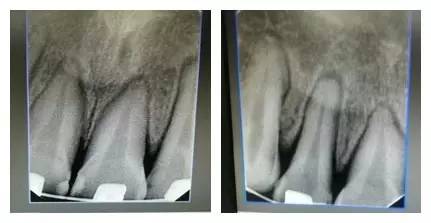

由上圖可知,患者全口牙齒磨耗較重,尖牙牙尖磨耗,無法起到引導(dǎo)和保護(hù)作用,上前牙牙根短,上中切牙腭側(cè)面邊緣嵴消失,

由此推斷:尖牙牙尖磨耗,患者在前伸(牙合)運(yùn)動(dòng)時(shí),引導(dǎo)不足,前牙的接觸面過大,受力較大;患者在側(cè)方(牙合)運(yùn)動(dòng)時(shí)下前牙沒有了引導(dǎo),會(huì)直接對(duì)側(cè)切牙造成撞擊;再加上前牙根較短,無法耐受,引起(牙合)創(chuàng)傷,繼發(fā)牙髓癥狀;失去尖牙保護(hù)(牙合),加重了牙齒的磨耗。

以上群里多位醫(yī)生的探討基本與權(quán)老師的處理方案接近。權(quán)老師的最終治療是通過樹脂暫時(shí)恢復(fù)尖牙引導(dǎo)功能,側(cè)方引導(dǎo),使上下前牙分離了,緩解前牙創(chuàng)傷;做完舌側(cè)的功能恢復(fù),后牙打開較多,在某種程度上對(duì)后牙也有很大保護(hù)。